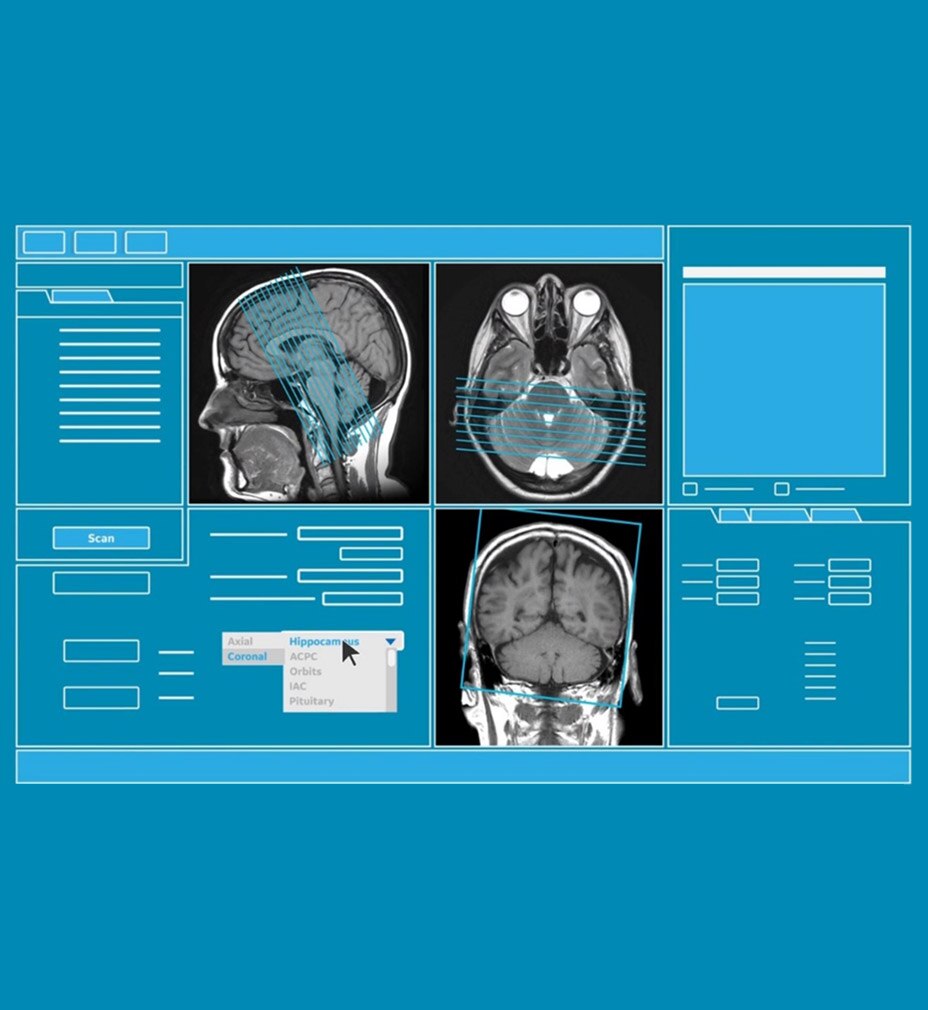

KULLANICI ARAYÜZÜ

Otomatik olarak sezgisel

Revolution Ascend'i kullanıma sunarak, birinci sınıf BT sistemimizle aynı kullanıcı arayüzünü (UI) dahil ediyor ve işlevleri standartlaştırmaya başlıyoruz. Kullanıcı Arayüzü, akıllı anatomi tanıma ve lokalizör ayarları için Smart Plan gibi özelliklerle günlük ihtiyaçlarınız düşünülerek tasarlanmış yeni Clarity Operatör Ortamına sahiptir. Ek olarak Auto Prescription, uzmanlık düzeyinizden bağımsız şekilde hastaya özel tarama parametreleri önererek tarama kurulumunu ayarlar ve tüm taramalarda istenen görüntü kalitesi ve doz performansını sağlar.